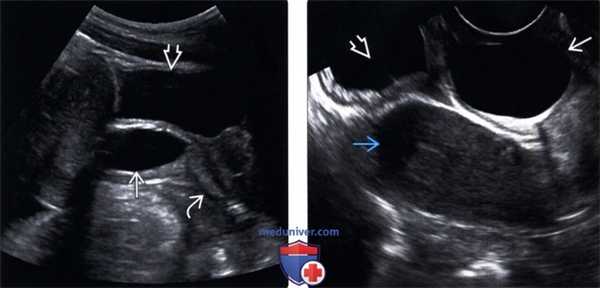

(Левый) На сагиттальном трансабдоминальном УЗ срезе таза в верхнем отделе влагалища визуализируется овальная киста. Нижний отдел влагалища и мочевой пузырь в норме.

(Правый) На продольном трансвагинальном УЗ срезе (эта же пациентка) с минимальным давлением киста кажется более круглой. Матка и мочевой пузырь в норме.

(Левый) На продольном трансвагинальном УЗ срезе с цветовой допплерографией у этой же пациентки отсутствует цветовой ток в кисте гартнерова хода.

(Правый) На парасагиттальном Т2 FS МР срезе визуализируется однокамерная Т2-усиленная киста гартнерова хода в верхнем отделе влагалища. Мочевой пузырь и матка без изменений.